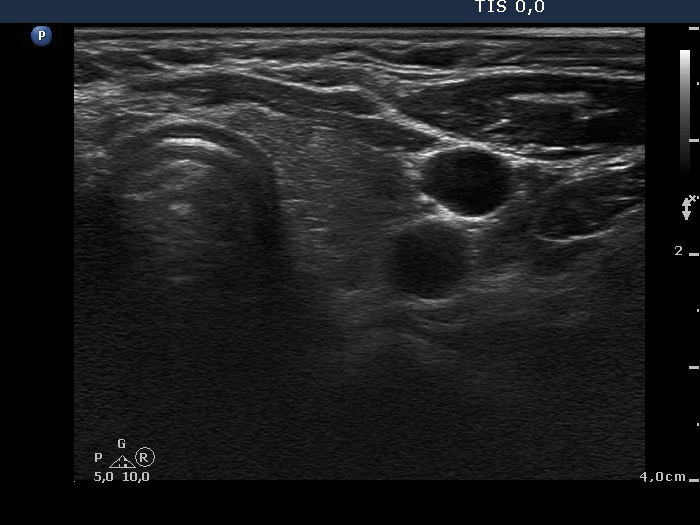

Discrete lesion or nodule in Hashimoto's thyroiditis - case 17 (782) (ultrasonographic picture 7)

Right lobe, longitudinal scan